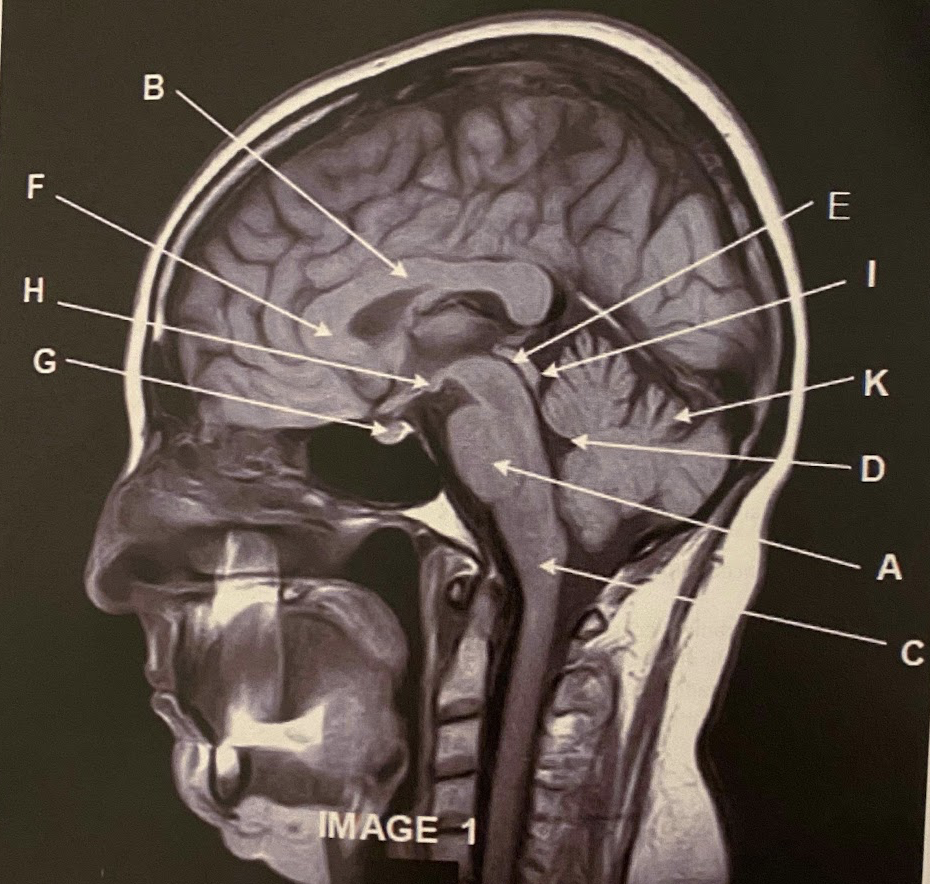

The sagittal scan, demonstrates typical hyper intense tendril-like projections in the corpus callous characteristically seen in patients with what disease?

C) Multiple Sclerosis

What anatomy is letter A pointing to?

Pons

What anatomy is letter B pointing to?

Corpus Callosum

What anatomy is letter C pointing to?

Medulla Oblongata

What anatomy is letter D pointing to?

Fourth ventricle

What anatomy is letter E pointing to?

Aqueduct of Sylvius

7

What anatomy is letter F pointing to?

Genu of the corpus callous

Q

A

Pituitary

Mammillary Bodies

10

What anatomy is letter I pointing to?

Quadrigeminal plate

This image is non-contrasted. It was acquired using a _______ sequence

C) FLAIR